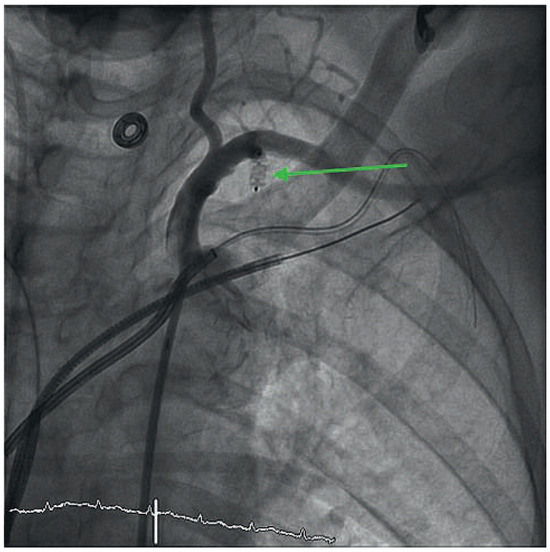

Anterior ST-Elevation Myocardial Infarction After Excimer Laser Extraction of Defibrillator Leads

by Reto Berli, Jürg Grünenfelder and Christophe Wyss

We describe a case of a so far unknown complication after failed extraction of defibrillator leads. Perforation of the LIMA bypass caused by Excimer laser created an arterio-venous fistula from the proximal bypass to the superior subclavian vein and occlusion of the distal [...] Read more.

We describe a case of a so far unknown complication after failed extraction of defibrillator leads. Perforation of the LIMA bypass caused by Excimer laser created an arterio-venous fistula from the proximal bypass to the superior subclavian vein and occlusion of the distal LIMA bypass with consecutive anterior S T-elevation myocardial infarction. Full article